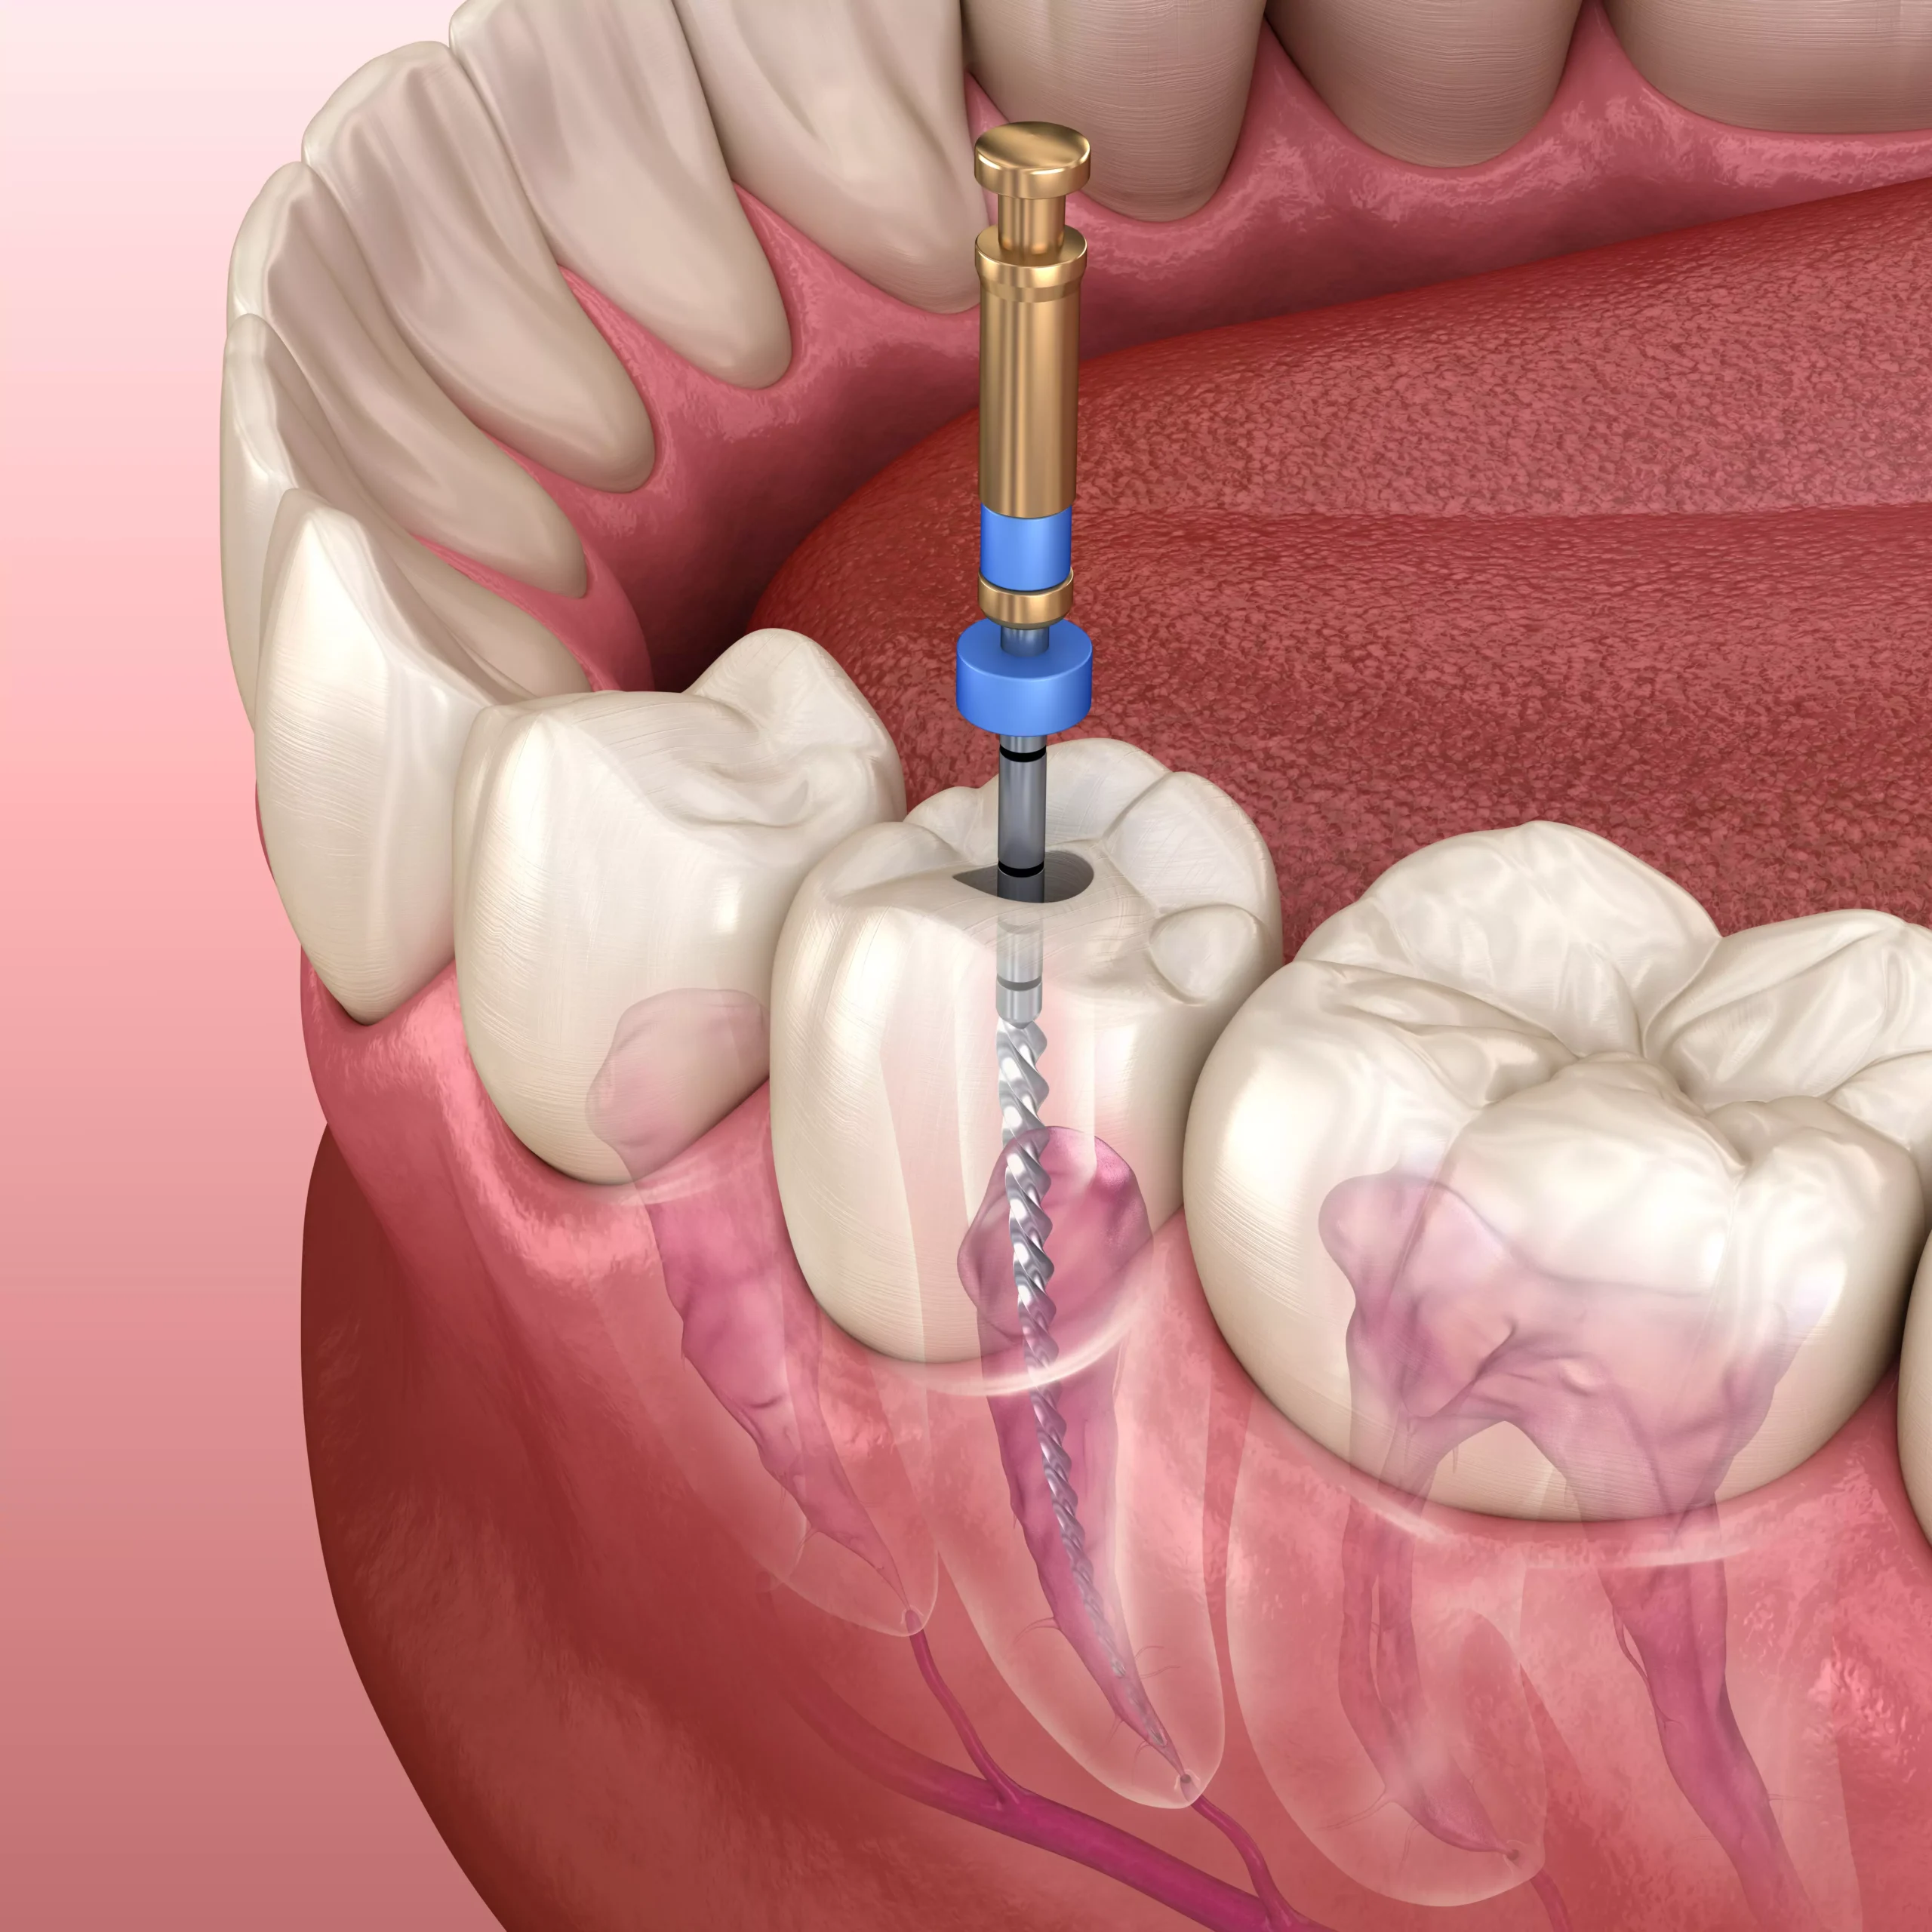

Leczenie kanałowe jest specjalistyczną procedurą stomatologiczną, która polega na usuwaniu zainfekowanej tkanki oraz nerwu znajdujących się wewnątrz zęba.

Jest to często konieczne w przypadku zaawansowanej próchnicy lub uszkodzenia zęba, co ma na celu zachowanie jego struktury i funkcji.

Leczenie kanałowe, nazywane również endodoncją, jest procedurą mającą na celu usunięcie zainfekowanej tkanki oraz nerwu z wnętrza zęba.

Po dokładnym wyczyszczeniu kanałów korzeniowych z bakterii, kanały te są dezynfekowane i szczelnie wypełniane, co zapobiega dalszym infekcjom i utrzymuje integralność zęba.

Jak przy każdym zabiegu medycznym, istnieje ryzyko powikłań, takich jak złamanie narzędzia endodontyczego czy perforacja kanału, jednak przy leczeniu pod mikroskopem takie powikłania są rzadkością.

Czas trwania leczenia kanałowego zależy od skomplikowania przypadku. Proste przypadki wykonywane są na jednej wizycie, podczas gdy bardziej złożone mogą wymagać kilku sesji.